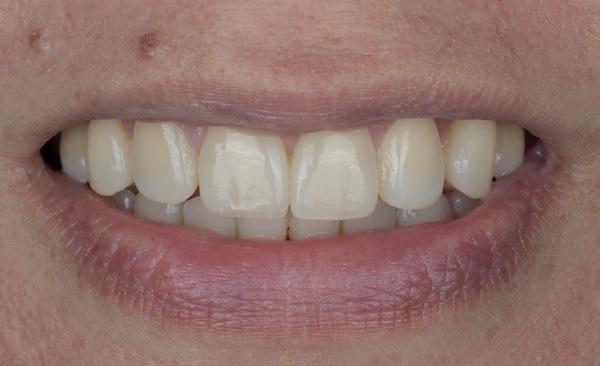

Een 47-jarige vrouw wordt aan het einde van het orthodontische traject door haar eigen tandarts naar mij verwezen voor een intake en eventuele behandeling. Bij mevrouw zijn elementen 12 en 22 afwezig. De 13 en 23 zijn gemesialiseerd. Haar eigen tandarts vraagt of ik het front met composiet kan restaureren om weer een harmonieuze glimlach te krijgen (Afbeelding 1).

Tijdens de intake wordt een complete lichtfoto status gemaakt om de positie van de elementen goed in kaart te brengen en een behandelplan op te kunnen stellen. Op de close-up foto van het bovenfront (afbeelding 2) zien we dat er sprake is van slijtage aan element 11. Elementen 12 en 22 zijn afwezig en elementen 13 en 23 zijn gemesialiseerd. Tussen element 11 en 13 is er sprake van een diasteem. Dit diasteem is niet aanwezig aan de andere zijde (afbeelding 3).

Dit zorgt voor een lastige situatie, omdat bij het sluiten van dit diasteem (dit is de wens van de patiënt) elementen 13 en 11 breder zullen worden dan elementen 21 en 23. Dit is één van de redenen waarom ik patiënten altijd graag aan het einde van het orthodontist traject wil zien. Op dat moment is het nog mogelijk om kleine wijzigingen door te voeren, voordat de beugel definitief wordt verwijderd. Na de intake stuur ik een terugrapportage naar de orthodontist waarbij ik vraag om de elementen zo te positioneren dat de ruimte beter verdeeld is.

Ik zie mevrouw een aantal weken later terug voor evaluatie (afbeelding 4). Er is een klein centraal diasteem ontstaan en daardoor is het diasteem tussen de 11 en 13 ook kleiner geworden. Tussen de 21 en 23 is geen diasteem aanwezig (afbeelding 5), waardoor er hoogstwaarschijnlijk wel iets breedte verschil zal zijn tussen de linker- en rechterzijde.

Met composiet wordt een snelle mock-up gemaakt om te beoordelen of ik in deze situatie goed kan uitkomen met de ruimte, of dat we wellicht de elementen nog meer moeten verplaatsen (afbeelding 6). Mevrouw is zeer tevreden met de snelle mock-up en daarom wordt besloten dat de orthodontische behandeling afgerond kan worden. Eventuele verschillen in breedte kunnen we proberen optisch zoveel mogelijk te maskeren.

Nadat de vaste apparatuur verwijderd is (afbeelding 7 en 8), zie ik mevrouw voor het maken van een afdruk/scan ten behoeve van een wax-up. Aangezien ik in deze casus wil werken met de injectietechniek, is een wax-up noodzakelijk.